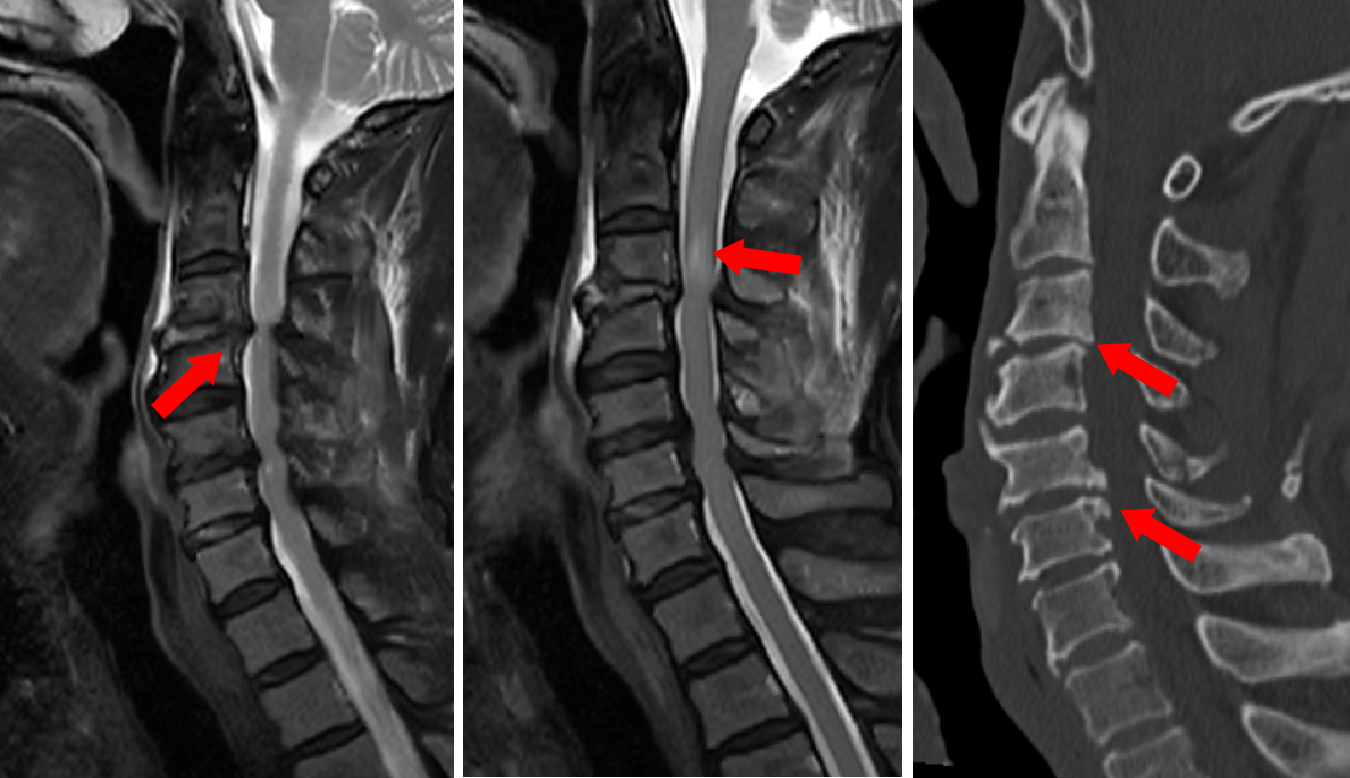

图2 MRI和CT见脊髓受压水肿及骨刺等

术中,张培海医生协同孙振兴医生凭借熟练的手术技艺,彻底清除了压迫患者脊髓和神经根的血肿、椎板及韧带组织,显微镜下充分减压,患者脊髓搏动逐步恢复,神经外科团队通过螺钉和连接棒固定重建了患者的颈椎稳定性。为了避免患者术后因凝血功能障碍出现术区血肿,手术团队在显微镜下反复检查核对,保证术区无活动性出血,留置术区引流后,关闭切口。患者手术非常顺利,转入重症监护室后经过密切监测治疗,第二天成功拔除了气管插管,未出现大出血、呼吸衰竭及截瘫等并发症。